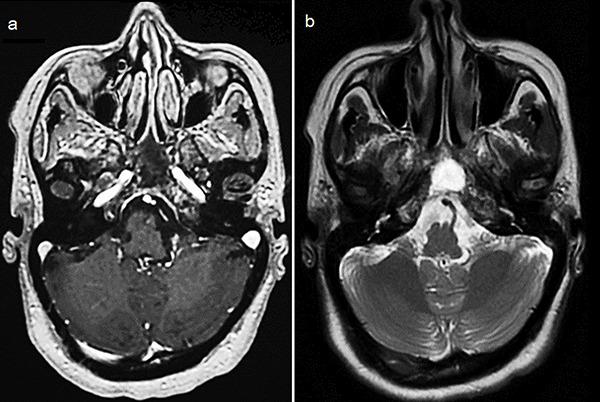

Plasmacytoma is a rare plasma cell neoplasm. Whether solitary or associated with multiple myeloma (MM), it rarely involves the skull base, particularly the sphenoid bone. We present a unique case of sphenoid bone plasmacytoma secondary to MM, highlighting diagnostic and therapeutic challenges. A 56-year-old female presented with headaches, vomiting, epistaxis, and cranial nerve deficits. Cerebral imaging revealed a 65-mm tumor infiltrating the sphenoid bone and adjacent structures. Subtotal resection was performed using an endoscopic nasal approach. Histopathology revealed plasmacytoma, and diagnostic workup confirmed MM. By the end of biological exploration, relapse of the sphenoid plasmacytoma was observed, and the patient was successfully treated with radiotherapy, immunochemotherapy, and autologous stem cell transplantation. After 18-month follow-up, sustained complete remission was confirmed. Although rare, the diagnosis of plasmacytoma should be considered in cases of skull base tumors. This localization is highly predictive of MM, warranting comprehensive investigations to initiate prompt and adequate management.

浆细胞瘤是一种罕见的浆细胞肿瘤。无论是孤立性还是与多发性骨髓瘤(MM)相关,它很少累及颅底,尤其是蝶骨。我们报告一例继发于MM的蝶骨浆细胞瘤的独特病例,突出诊断和治疗挑战。一名56岁女性出现头痛、呕吐、鼻出血和颅神经功能缺损。脑部影像学检查发现一个65毫米的肿瘤浸润蝶骨及相邻结构。采用鼻内镜入路进行了次全切除。组织病理学显示为浆细胞瘤,诊断检查证实为MM。在生物学检查结束时,观察到蝶骨浆细胞瘤复发,患者接受放疗、免疫化疗和自体干细胞移植后成功治愈。经过18个月的随访,确认持续完全缓解。尽管罕见,但在颅底肿瘤病例中应考虑浆细胞瘤的诊断。这种定位高度提示MM,需要进行全面检查以便及时进行充分治疗。